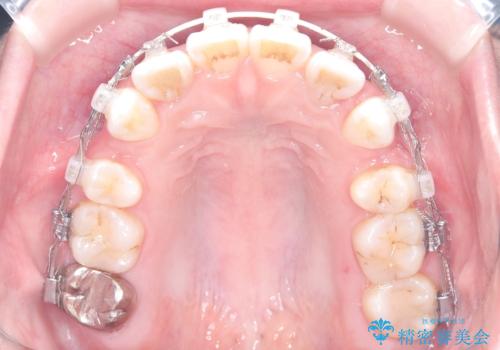

治療は、審美ワイヤーを用いて抜歯スペースを徐々に閉じながら、前歯の角度と位置を精密にコントロールして進められました。ワイヤー矯正は歯を三次元的にしっかりと動かすことができるため、前歯を単に倒すのではなく、根元から理想的な位置へと誘導しました。

1年半の治療期間を経て、抜歯したスペースは完全に閉じ、突き出ていた前歯はすっきりと内側に収まりました。噛み合わせの精度も向上し、機能面でも良好な結果が得られています。